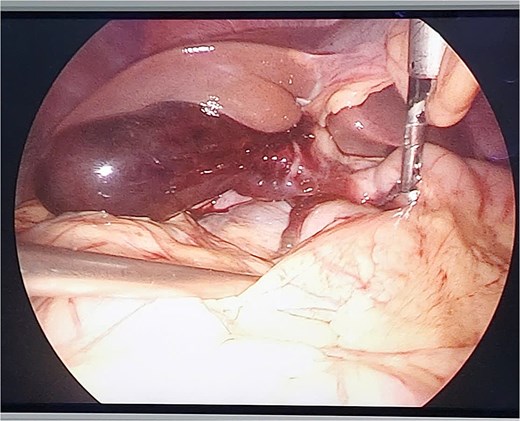

The patient was indicated for diagnostic laparoscopy. During laparoscopic surgery, gallbladder contusion was found and there was a presence of free blood in the peritoneal cavity, but no hollow organ rupture was observed (Fig. 2).